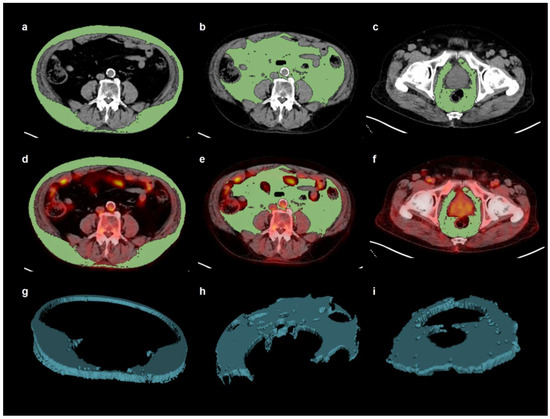

2.3. Image Analysis